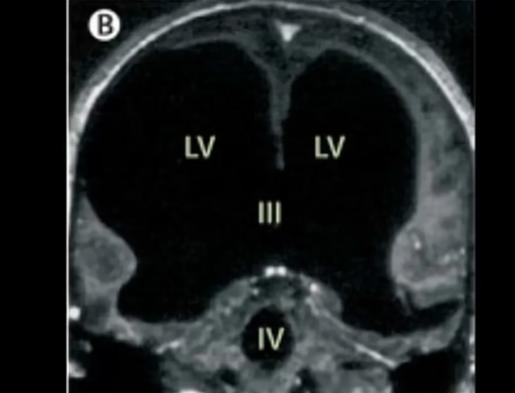

法国惊现“无脑”人!一男子在做脑部检查时,医生惊讶的发现男子居然没有大脑,但他的身体却十分的健康,并且还考上了公务员,如今还是两个孩子的爸爸。   想象一下,一个44岁的男人,是两个孩子的父亲,是一名兢兢业业的公务员,每天朝九晚五,还能考上公务员这种“铁饭碗”。   但在一次意外检查中,医生拿着他的脑部CT片子,手都在抖——片子上黑乎乎一片,全是水!   哪有什么大脑?正常人的大脑组织哪去了?   这不是科幻片,这是发生在法国马赛医院里的真实一幕,主角叫奥利维。   当时,奥利维因为左腿莫名疼痛去医院,本以为是腰间盘突出或者肌肉拉伤,结果医生一看核磁共振,全场死寂。   影像显示,他的颅腔里90%的空间都被脑脊液填满了!   原本应该饱满的大脑灰质、白质,被挤压得像纸片一样薄,紧紧贴在头骨内侧,厚度不足1毫米。   说得直白点,他的脑子里除了水,几乎啥都没剩。   按常理,这种重度脑积水患者,别说考公务员了,能不能活过婴儿期都是问题。   可奥利维不仅活了,还活得挺好:智商测出来75,虽然比普通人(80-100)稍低一点,但完全不影响生活,甚至还能处理复杂的公务员文书工作。   医生们彻底懵了:这不符合科学啊!难道我们以前对大脑的认知全是错的?   随着病史被挖出,真相更让人后背发凉。   原来,奥利维半岁时就得了严重的脑积水,当时医生给他做了分流手术,插了根管子把脑子里的水排出去。   到了14岁,医生看他发育正常,就把管子拔了。   谁能想到,这根管子一拔,病魔就开始了“慢刀子杀人”。   接下来的30年里,脑脊液悄悄回流,一点点侵蚀他的脑组织。   就像温水煮青蛙,他的大脑在不知不觉中被压缩、被替代,但他自己竟然毫无察觉!   没有头痛欲裂,没有瘫痪卧床,他就像正常人一样读书、工作、恋爱、生子。   如果不是这次腿疼,这个秘密可能要带进棺材里。   其实,他不只是个例。   早在1980年的英国,神经学家约翰·洛伯就遇到过更离谱的病例。   谢菲尔德大学有个数学系高材生,也是因为头疼去检查,结果CT扫描一出来,大脑几乎看不见,只在颅骨边缘有一层1.5毫米厚的脑灰质。   但他的智商高达125!数学成绩碾压一众学霸。   还有2016年《柳叶刀》记录的一位62岁女性,严重脑积水却意识清醒; 甚至有个叫诺亚的孩子,出生时脑组织只有常人的2%,医生劝妈妈放弃,结果人家不仅活下来了,三岁时脑容量还能长到正常人的80%。   这些案例把医学界的脸都打肿了,也把我们对“意识”的理解炸得粉碎。   为什么脑子都没了,人还能思考、有情感?   马赛医院的弗耶教授给出了一个大胆的解释:大脑的可塑性远超我们想象。   奥利维的大脑虽然被压扁了,但在长达30年的缓慢病变中,残留的脑组织——特别是脑干、基底神经节这些关键区域——可能“兼职”干了高级认知的活儿。   就像公司倒闭了,剩下的几个员工硬是把所有业务扛了下来,还运转得井井有条。   更神奇的是情感。奥利维的妻子说,丈夫虽然脑子“没了”,但特别会逗孩子笑,记得每一个结婚纪念日。   这种情感能力,似乎并不完全依赖于我们认为的“高级皮层”。   这也解释了为什么有的人中风切掉半个脑子,还能重新学会说话走路。   人类的大脑,可能天生就自带“极限备用方案”。   对此,你怎么看?